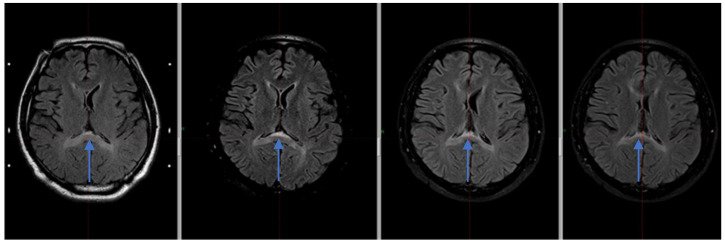

背景和临床意义:“回飞镖征”是指胼胝体脾部出现的回飞镖状细胞毒性水肿区。在MRI的t2加权图像、FLAIR和DWI上表现为高强度病变。目前还没有发现导致脾脏这些变化的具体病理机制;然而,作者列出了各种潜在的原因。病例介绍:本病例为一38岁男性患者,左脑桥小脑角肿瘤切除后,FLAIR MRI序列显示胼胝体内异常信号强度增高(回旋征)。在我们的病例中,与文献中描述的患者不同,连合的变化持续存在。结论:这些病变可能是由多种因素引起的,如小脑水肿和蛛网膜下腔出血的发展或在重症监护病房使用高渗盐。

Background and Clinical Significance: The term "boomerang sign" refers to a boomerang-shaped area of cytotoxic edema in the splenium of the corpus callosum. It is seen as hyperintense lesions on T2-weighted images, FLAIR and DWI in MRI. No specific pathomechanism leading to these changes in the splenium have been yet found; however, authors have listed a variety of potential causes. Case Presentation: The case presents a 38-year-old male patient after left cerebellopontine angle tumor resection with an abnormal, increased signal intensity within the corpus callosum (boomerang sign) in FLAIR MRI sequence. In the case of our patient, unlike the patients described in the literature, the changes in the commissure persist. Conclusions: These lesions could be caused by several factors such as the development of cerebellar edema and subarachnoid bleeding or hypertonic salt usage while in the intensive care unit.